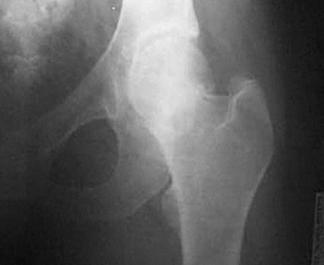

Luxatie de sold stang Luxatie de sold stang

Fractura

de cap femural Fractura de cap femural

Aspect

CT

de cap femural Fractura subcapitala cu usoara deplasare

Aspect CT

Fractura intertrohanteriana multifragmentara Luxatie de patela